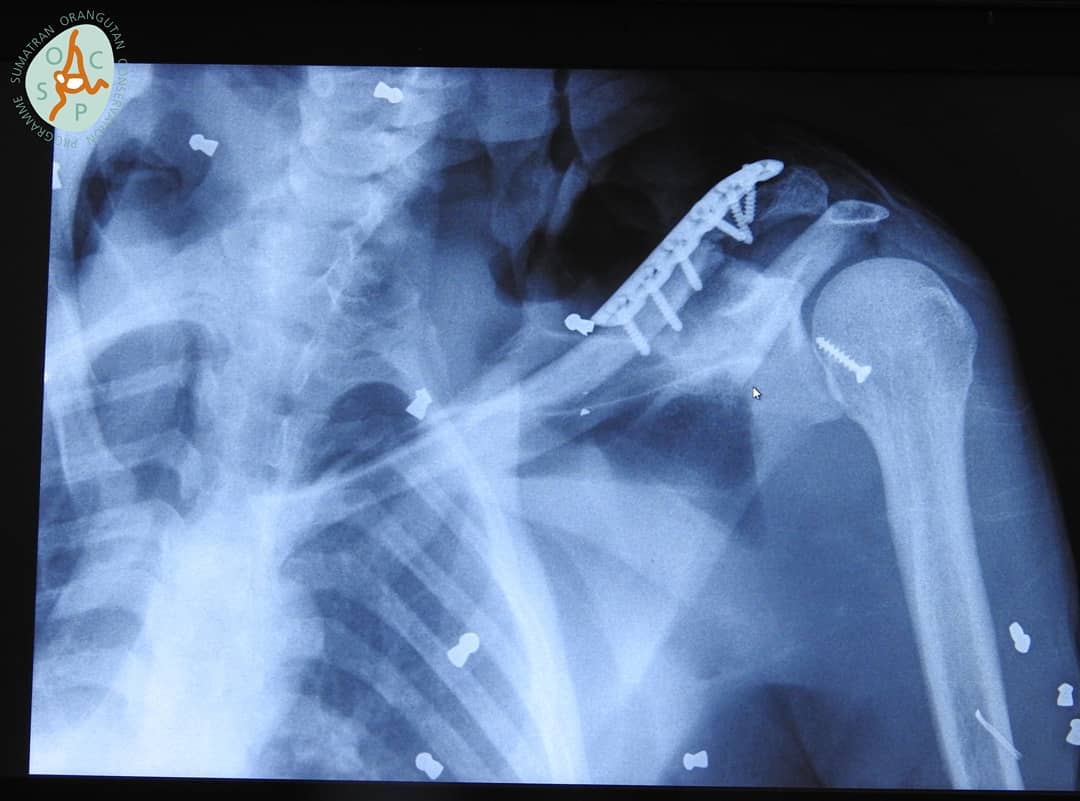

X-rays later revealed 74 air rifle bullets throughout her body, including in both eyes leaving her blind, as well as with broken bones. The severely wounded adult orangutan, named Hope by rescuers, was also nursing a seriously ill weeks-old baby when they were discovered in Aceh province’s Subulussalam district earlier this month.

Veterinarians went to work on 4-year-old Hope, removing pellets and fixing broken bones.